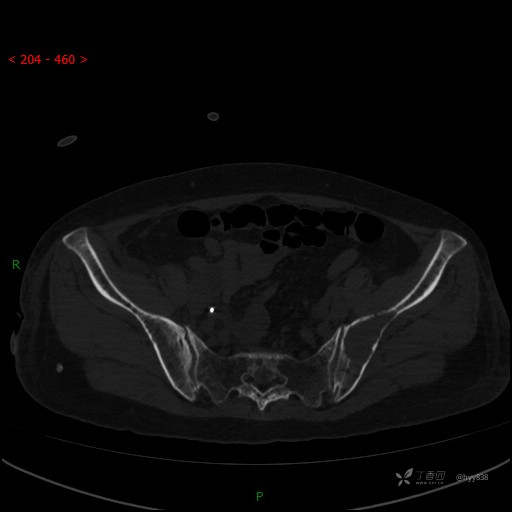

CT平扫

骨窗